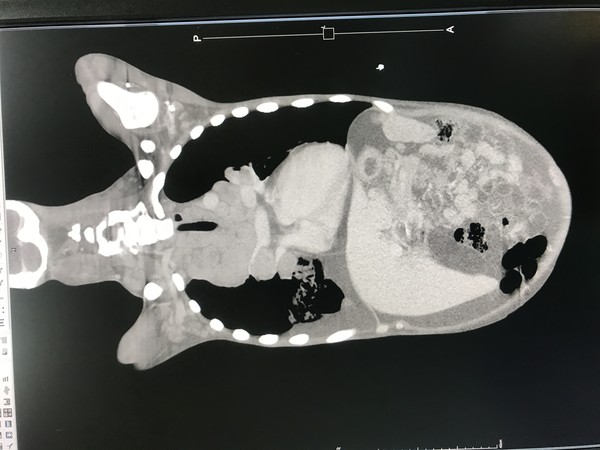

烏日林新醫院血液腫瘤科主任林增熙指出,楊姓患者早期只有頸部淋巴腫塊,由於延誤治療已久,就醫時左側脖子長了約4公分淋巴瘤,經切片化驗後確診,罹患惡性淋巴癌中佔10%盛行率的「何杰金氏淋巴瘤第4期」;從電腦斷層中發現癌細胞已轉移至淋巴結以外的器官,出現心包、胸腔、腹腔部位多處積水,甚至引起嚴重的心肺衰竭而轉至加護病房。

▲經由電腦斷層掃描檢查,顯示有心肺衰竭的情況。(圖/烏日林新醫院提供)